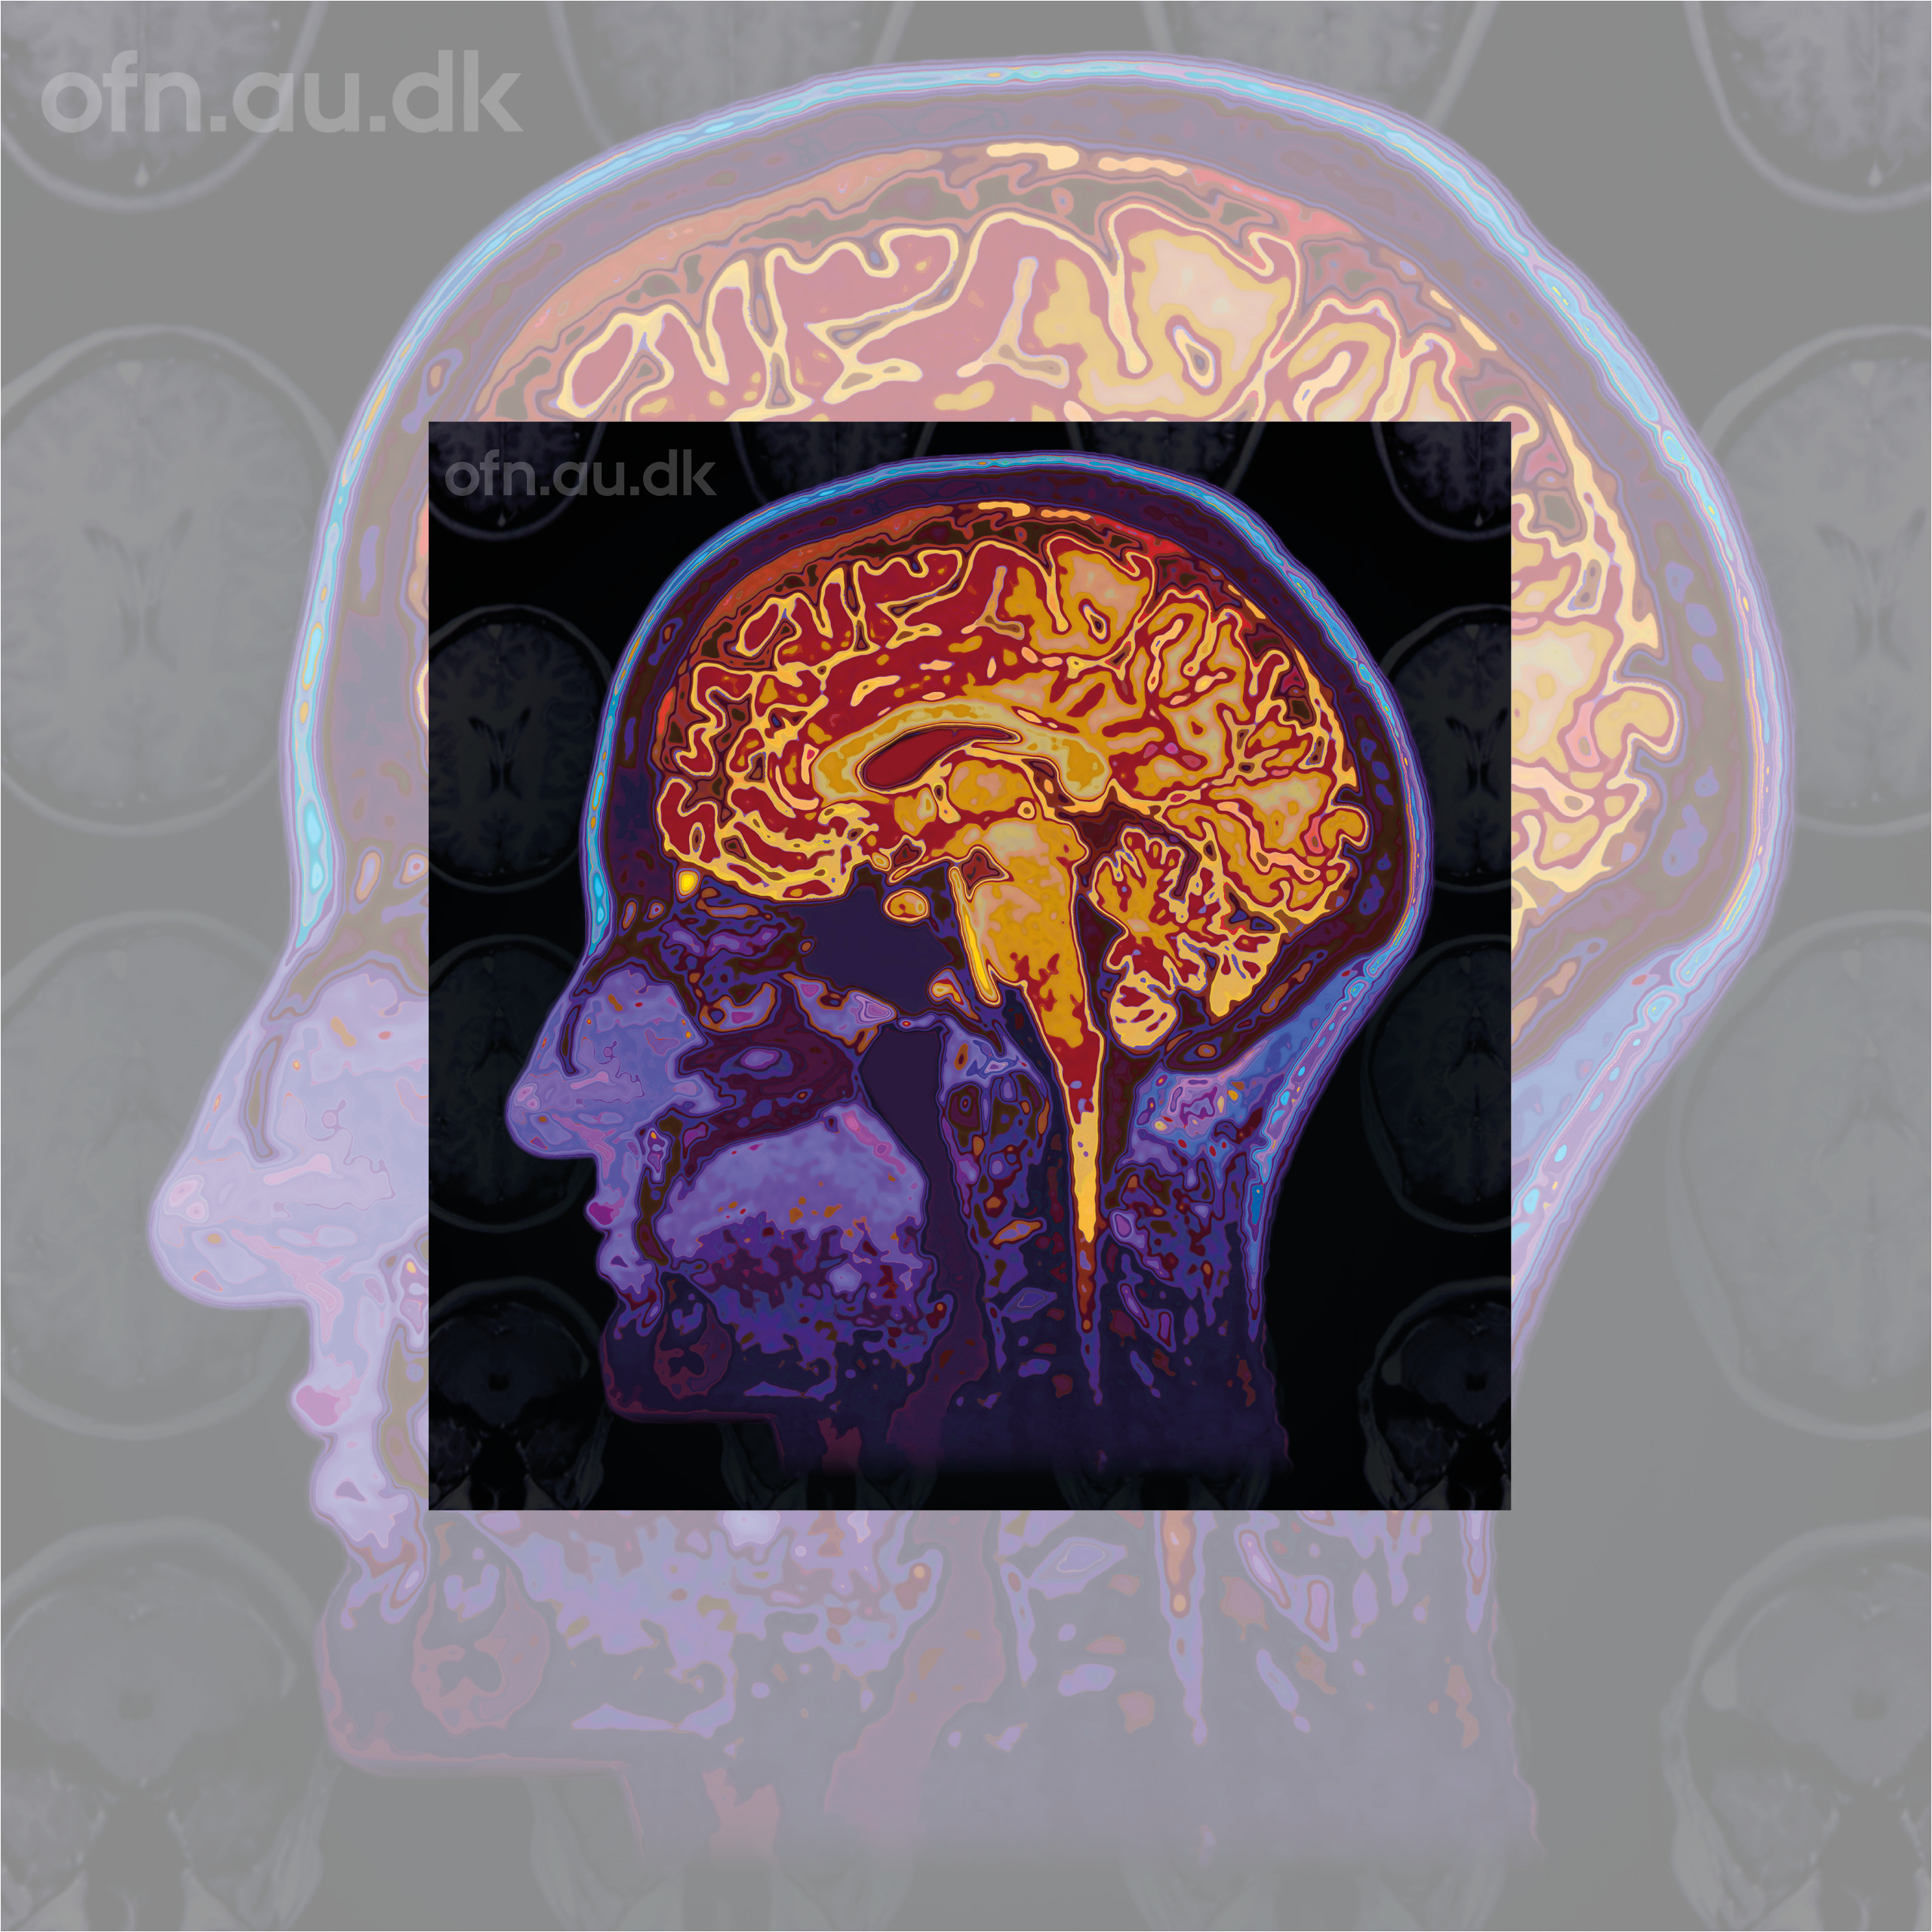

Foredraget vil præsentere de nyeste forskningsresultater fra computermodellering af hjerneskanninger, som måler aktivitet i levende menneskehjerner. Disse resultater giver indsigt i, hvordan musik, meditation og psykedeliske stoffer kan føre til forventningsglæde, nydelse og meningsfylde.